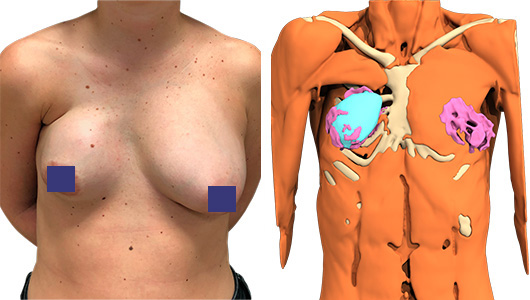

Vorne wird eine neuer, größerer Hohlraum für das neue weiche, mit Silikongel gefüllte Brustimplantat geschaffen. Remodellierung der tuberösen und ptosierten linken Brust mit periareolärer Dermo-Mastopexie.

Symmetrische Repositionierung des Warzenhofs der rechten Brust.

Das unmittelbare Ergebnis ist für den Patienten sehr zufriedenstellend (Abb.3). Die Thorax- und Brustsymmetrie ist stark verbessert.